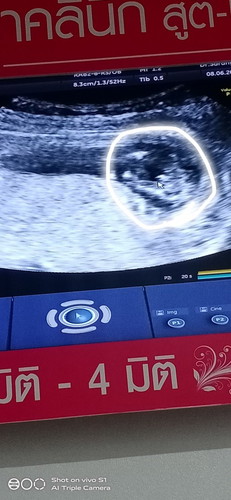

ขอสอบถามค่ะ ในใบซาวแม่ๆว่าเพศ ชาย รึ หญิงคะ 13สัปดาห์5วัน

อาจจะชายนะคะแม่เหมือนมีอะไรโผล่แต่ถ้าจะให้ชัวร์20wค่ะแม่เราซาวตอน20wเห็นจู๋ชัดมากค่ะ

น่าจะชายนะคะ เพื่อความชัวร์แนะนำให้ตรวจอีกทีตอน20วีคจะเห็นชัดค่ะ

13w เร็วเกินไปที่จะดูออกค่ะ นอกจากแม่ตรวจนิฟ ยืนยันเพศได้ชัดเจนค่ะ